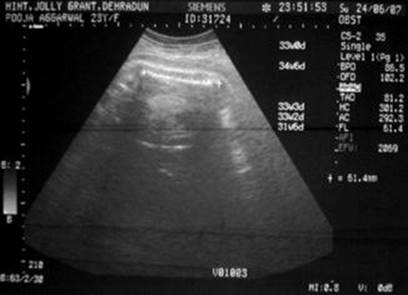

Fig. 3.7

Sonography of the same patient as in Fig. 3.6 showing femur length of 61.4 mm corresponding to 33 weeks of gestation with oligohydramnios [288]